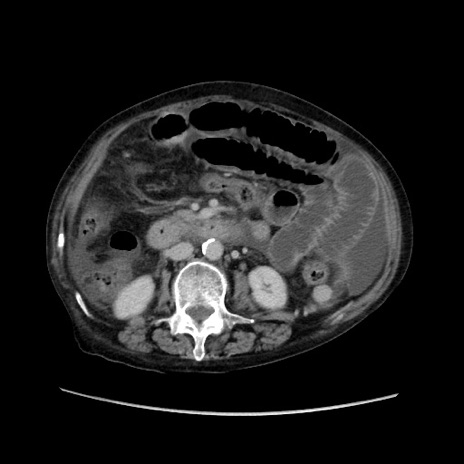

症例31(横断像)

【症例】80歳代 女性

【主訴】腹部膨満感

【現病歴】他院にて肝硬変にてフォロー中。1週間前から便秘、腹部膨満感、臍部腫瘤あり受診となる。

【既往歴】肝硬変

【身体所見】腹部膨隆あり、皮膚変化なし、疼痛なし。